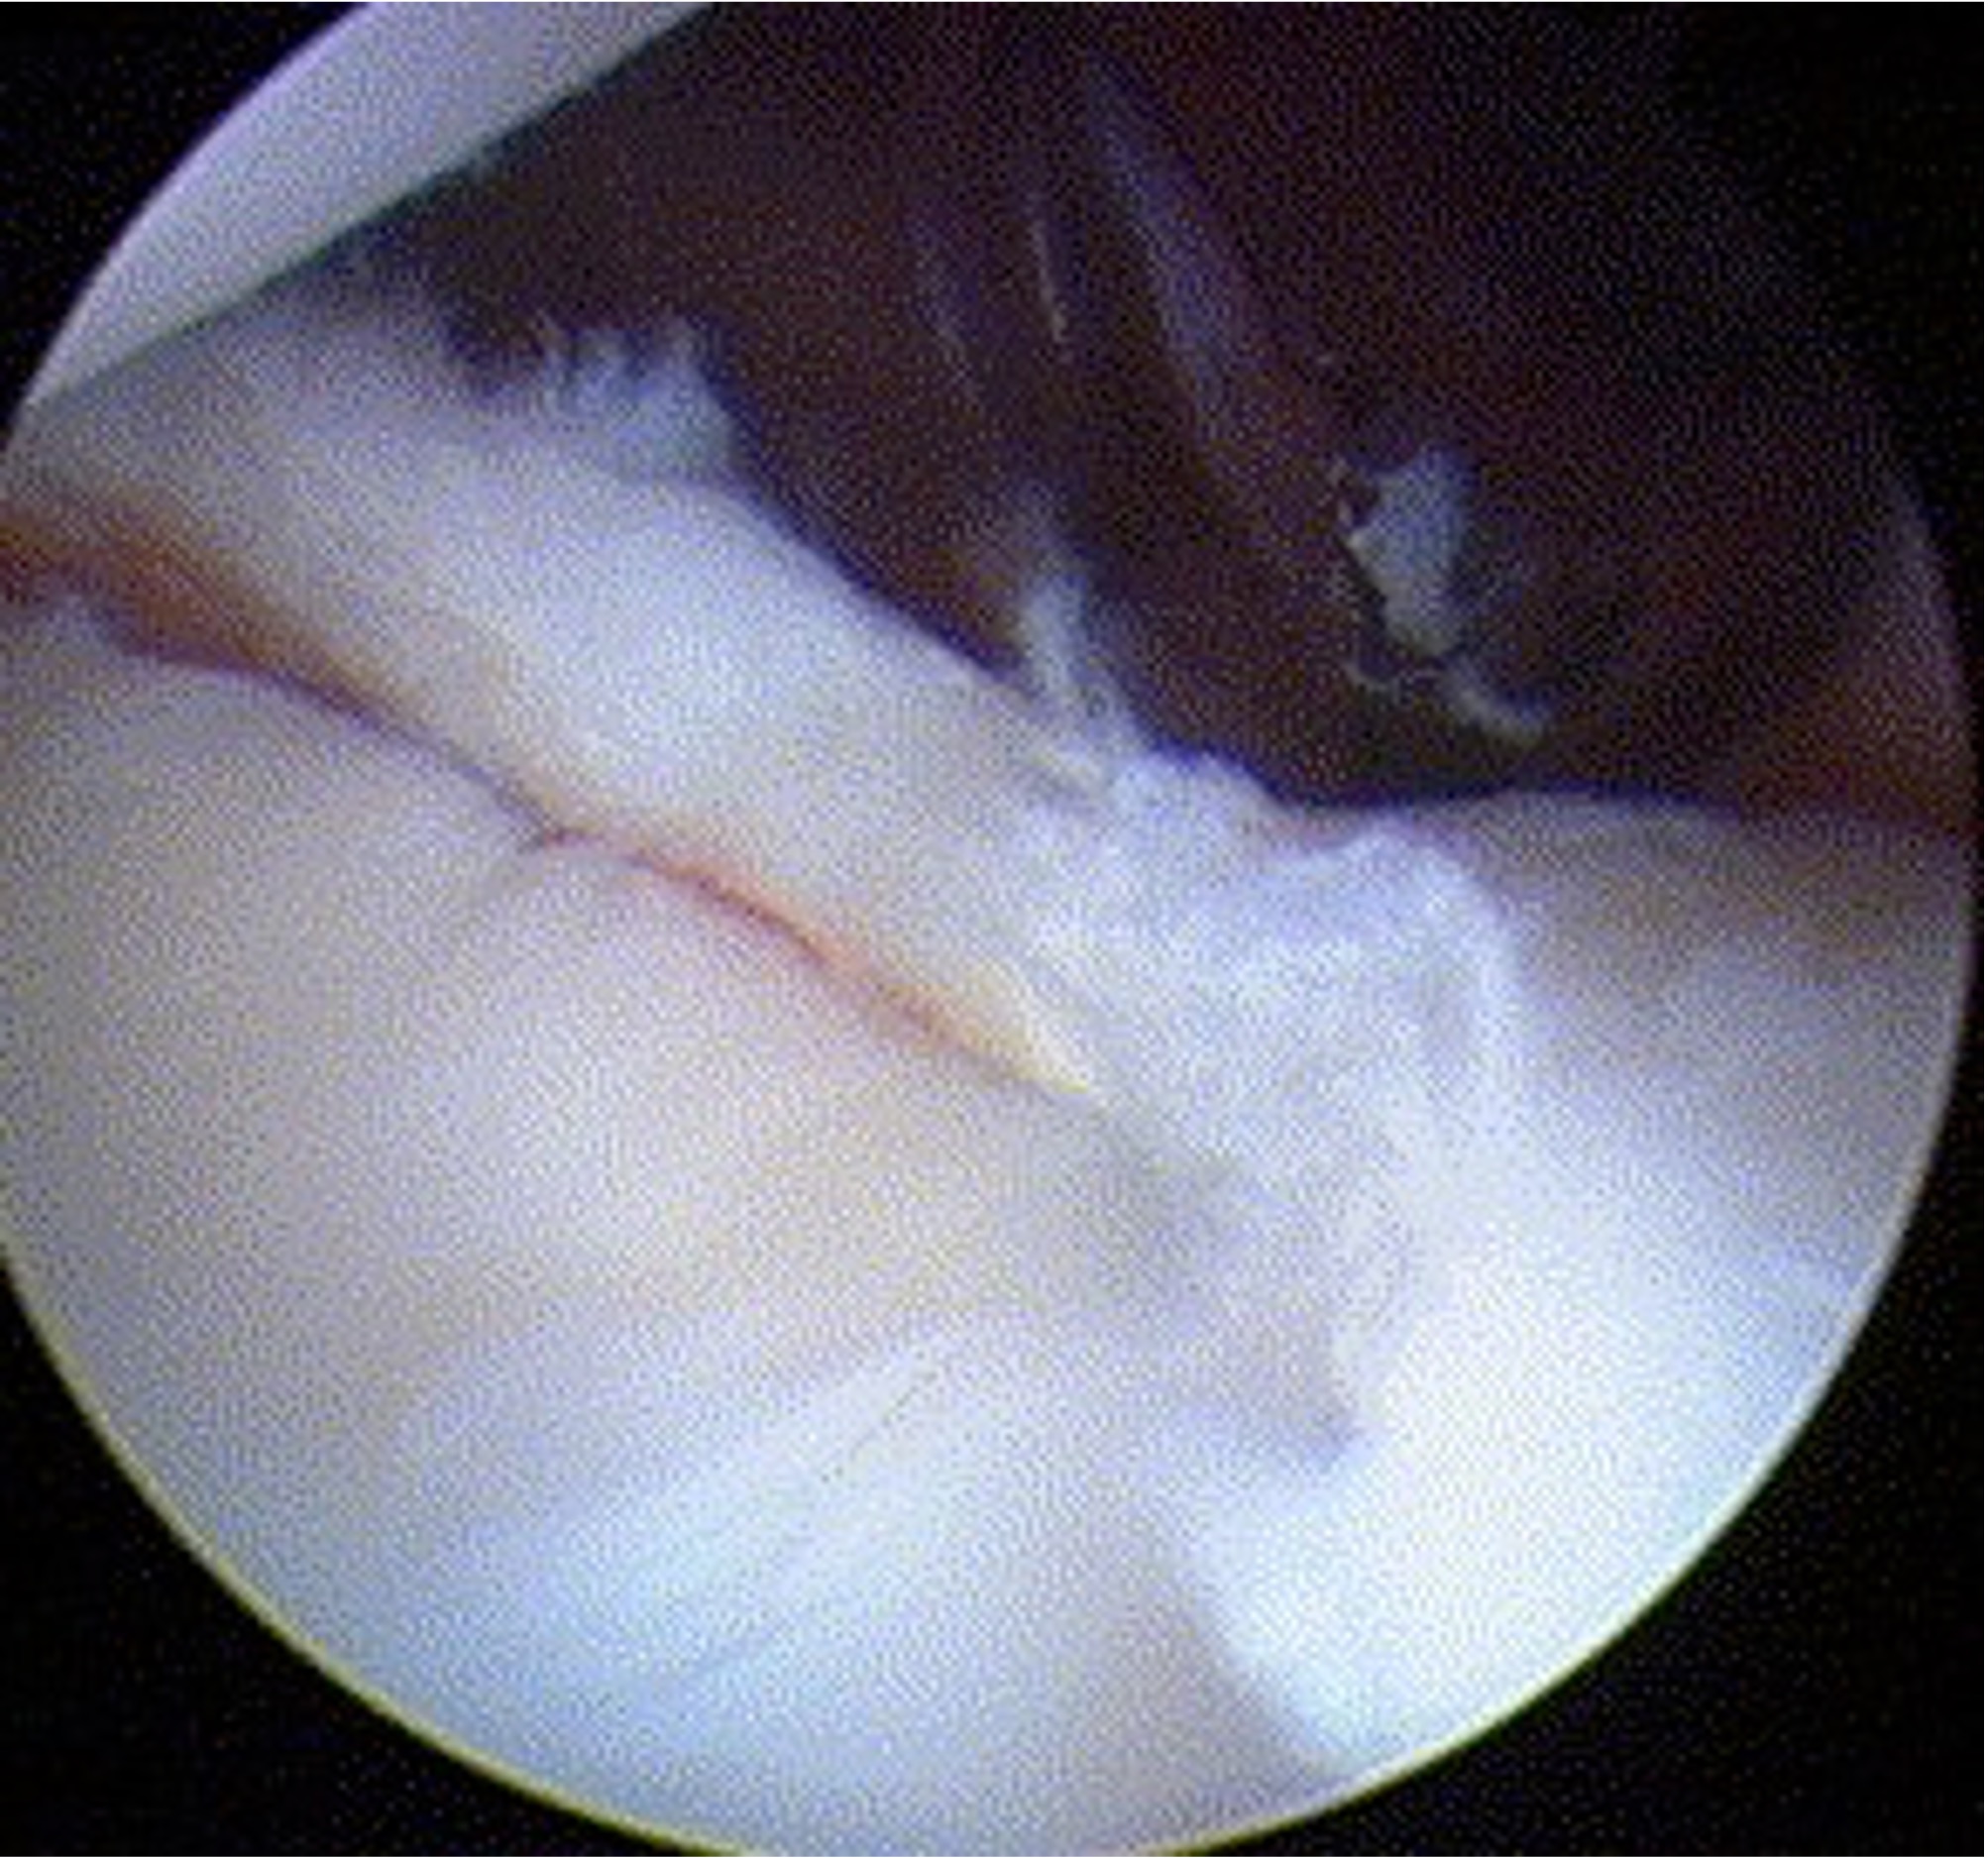

Glenoid assessment

Anterior chondral damage

Debride anterior glenoid bone to bleeding bone